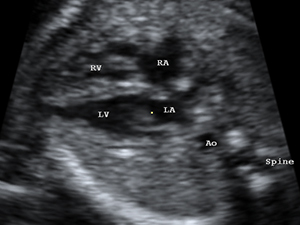

胎兒心臟四腔平面圖